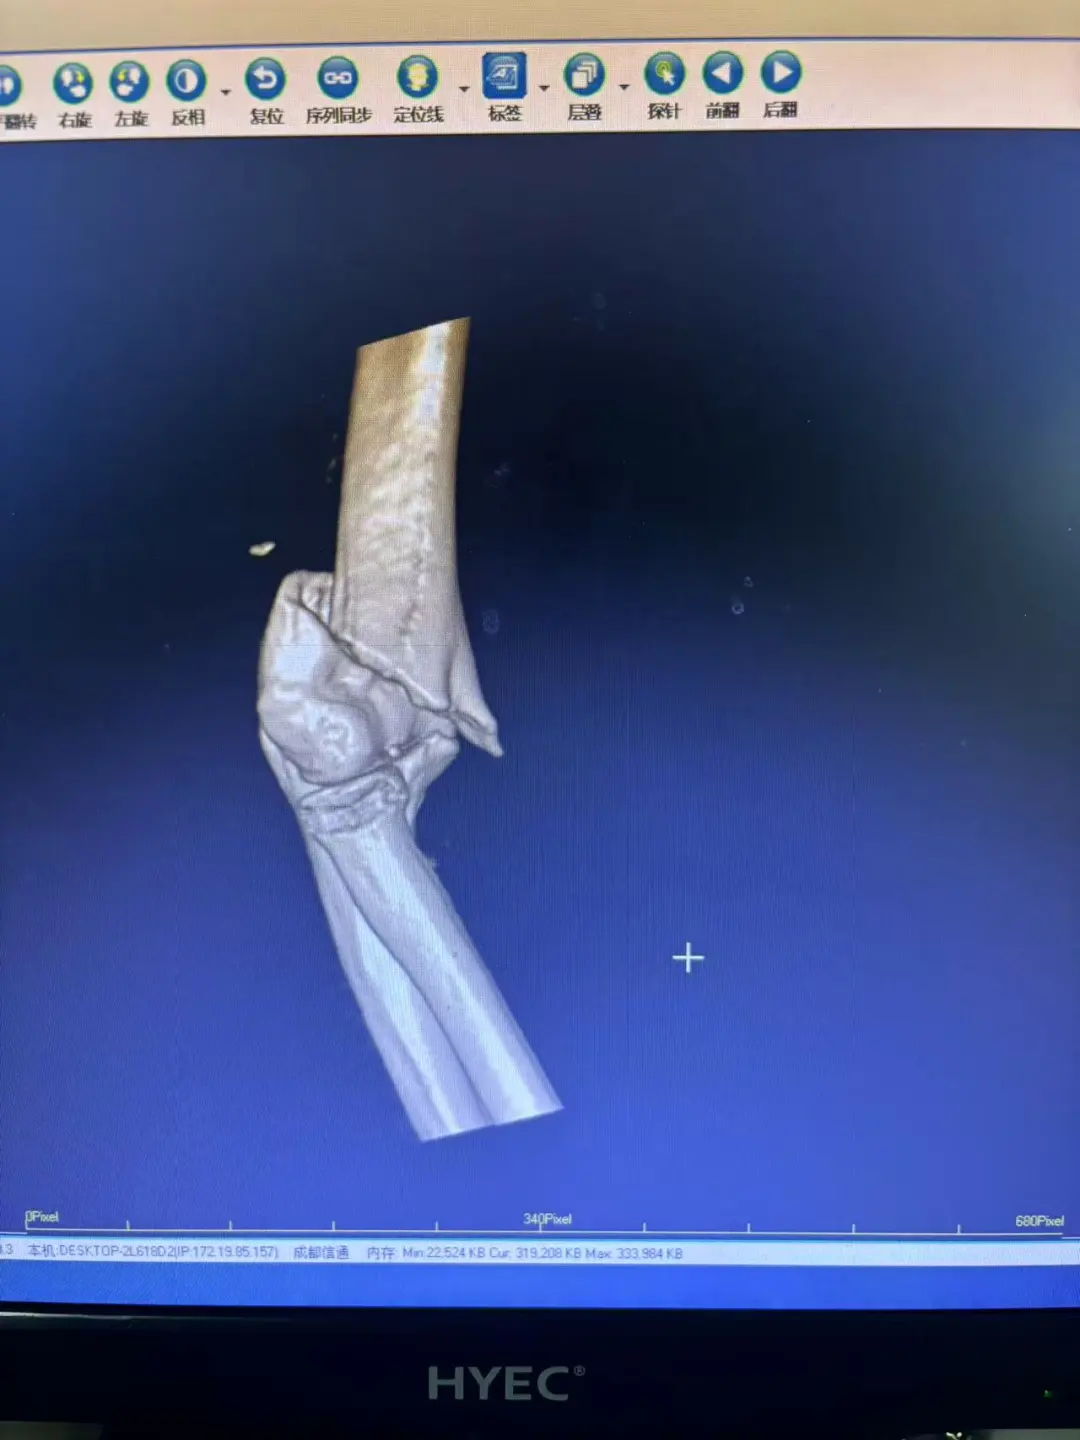

71歲的孫伯伯(化名)騎電動車時不幸與私家車相撞,當場傷情嚴重,被緊急送往我院救治。經(jīng)全面檢查,診斷結果為:右肱骨遠端粉碎性骨折,肘關節(jié)結構崩塌,若處理不當將面臨終身活動障礙;同時還合并閉合性顱腦損傷輕型、頭皮下血腫、左側肋骨骨折、腦萎縮及肺炎等多發(fā)傷病。

57分鐘后,手術圓滿成功。術后影像顯示,粉碎的關節(jié)面完美重建,內固定物位置精準。